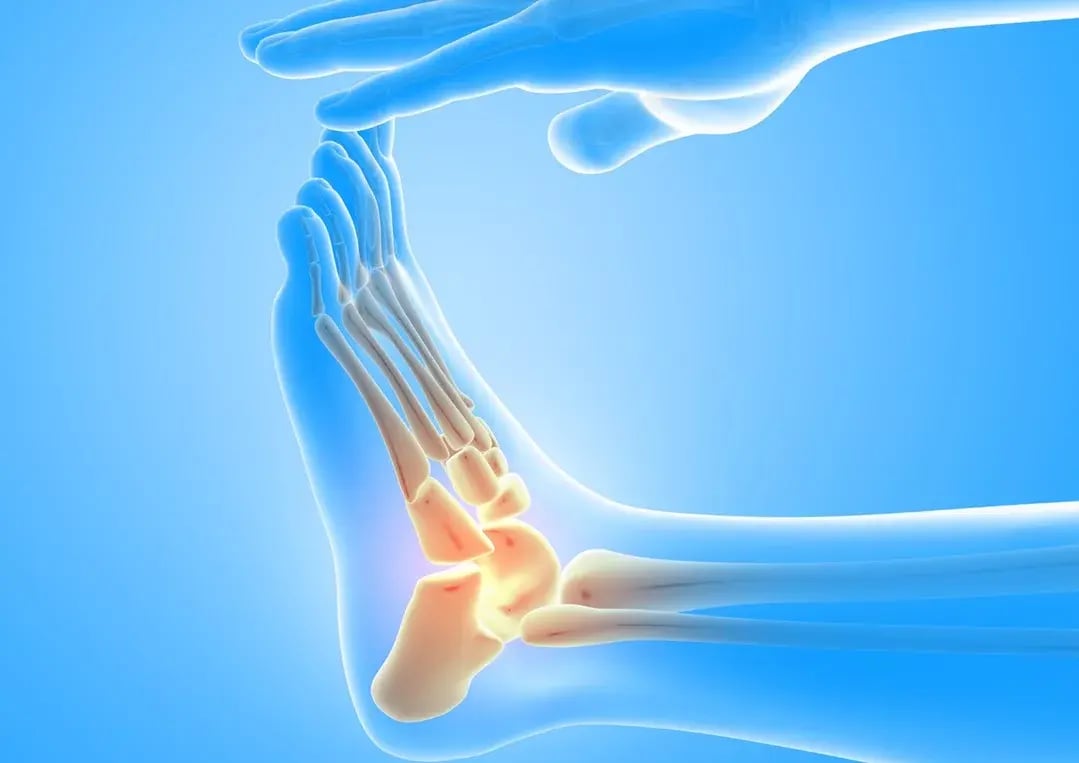

Plantar Fasciitis & Plantar Fibroma